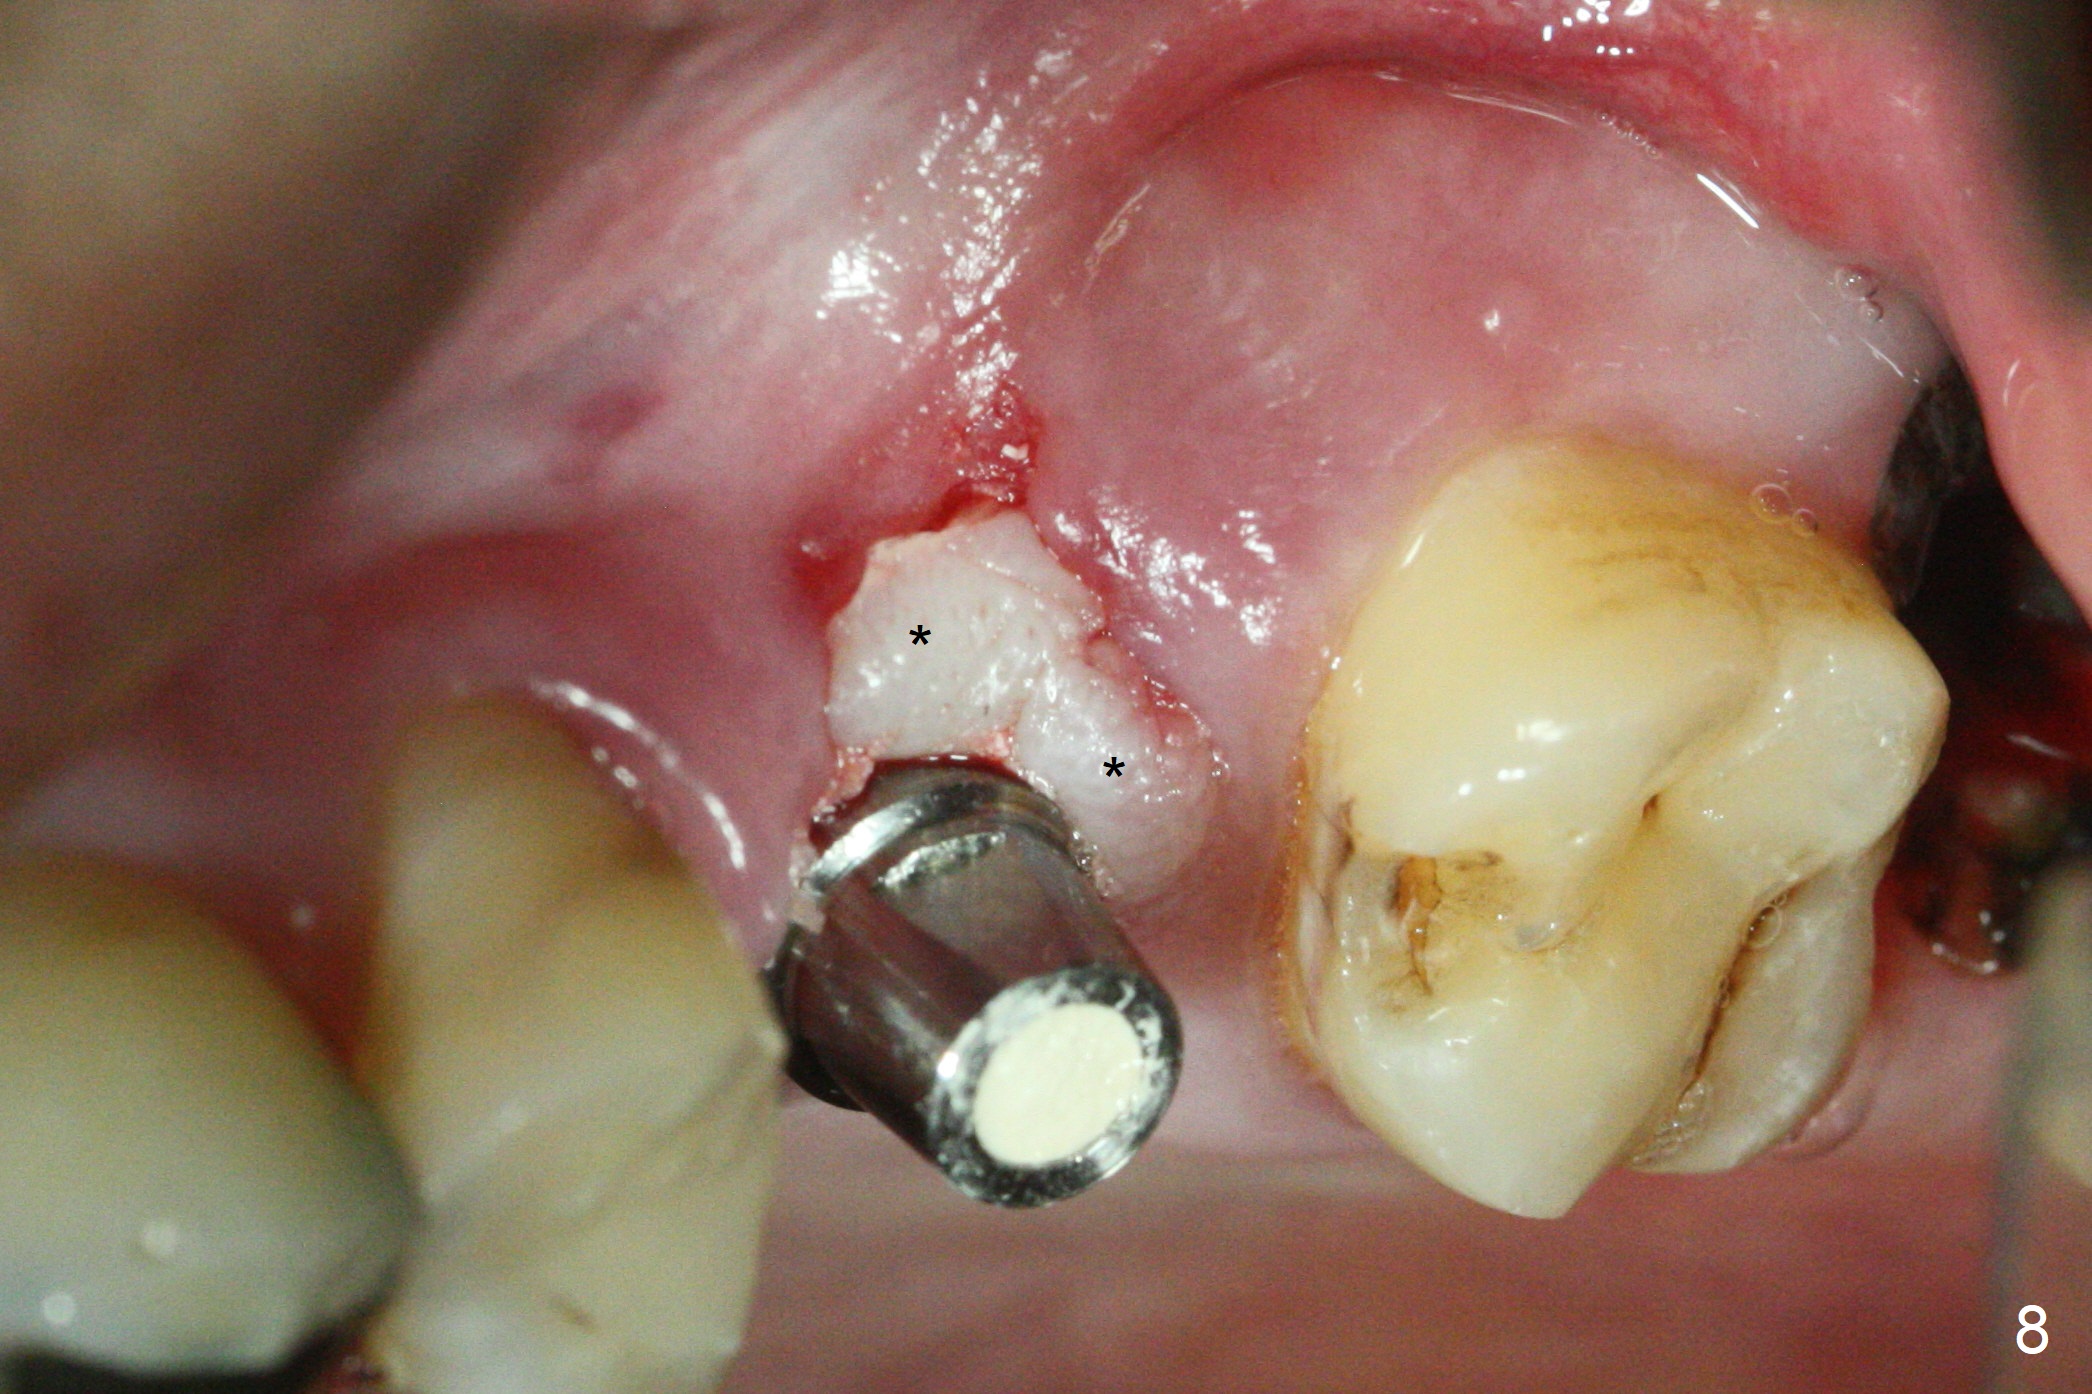

After extraction of the distobuccal residual root of the tooth #14 (Fig.1 arrow), the gingiva around the socket does not look like the keratinized one (Fig.2 *). An osteotomy through the distobuccal socket would seem too buccal for immediate implant. The palatal gingiva feels too tough to be stretched. An incision is made (Fig.3 dashed line); with elevation, the thick flap is transferred buccally (curved arrow). An osteotomy is initiated in the palatal bone with 1.5 mm drill, followed by Magic Expanders until 4.3 mm for 11 mm (Fig.4,5). Following Magic Drill 3.8x13 mm, the sinus membrane is found to be perforated. The latter is repaired with Osteogen plug. A 4.5x9 mm IBS implant is placed with 50 Ncm (Fig.6). Osteogen plug and allograft (Fig.7 *) are inserted into the remaining distobuccal socket (reduced after bone expansion). When a 5.5x4(4) mm abutment is placed, the transferred flap appears to be adapted to the distobuccal defect (Fig.8 *). Later one suture is placed for fixation. After provisional insertion, periodontal dressing is applied. Nine days postop, the periodontal dressing dislodges. When the loose provisional is removed for recementation, the flap seem to have healed (Fig.9 *). The gingiva heals around the abutment 5 months postop (Fig.9); the distal socket appears to heal while the bone graft remains at the crest (Fig.11,12). When #30 develops buccal abscess, the patient masticates on the left, leading to loss of composite at #13 (Fig.14); in fact the abutment at #14 is incompletely seated.